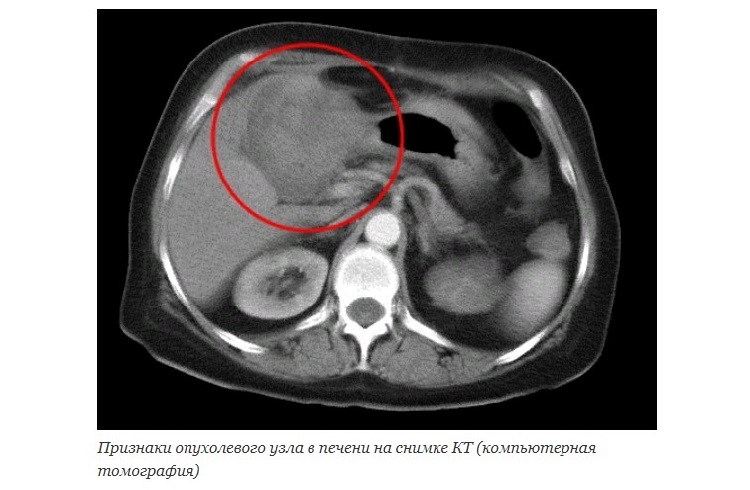

Инструментальные тесты

При очаговых образованиях в паренхиме печени на первый план выходят методы визуализации – то есть те исследования, которые позволяют оценить структуру ткани, выявить полости или иные объекты, не встречающиеся в норме:

- УЗИ ОБП (ультразвуковое исследование органов брюшной полости);

- КТ, МРТ (компьютерная, магнитно-резонансная томография);

- рентгенологические методики (обзорный снимок и тесты с использованием контрастирования);

- биопсия печени;

- ангиография.

В печени на УЗИ можно видеть гипоэхогенные образования с четкими контурами (при абсцессах, кистах) или объемные структуры (при опухолях). При этом формулировка «диффузно очаговые изменения печени» не является диагнозом, она лишь указывает на то, что затронута паренхима – причем не в одном, а как минимум в нескольких разных по локализации участках.